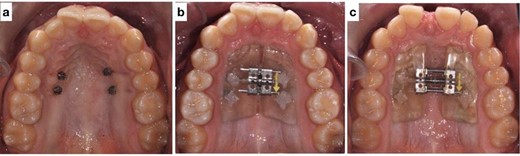

Treatment was initiated using a miniscrew-assisted rapid palatal expander to widen the upper arch by 4 mm (Fig. 4). The patient cooperated with maintaining oral hygiene, and the parents assisted with turning the expander. After expansion, the molars were banded, and the remaining teeth were bonded with 0.022" × 0.028" slot standard edgewise bands and Mclaughlin, Bennett and Trevisi (MBT) prescription brackets. Initially, both arches were leveled and aligned through thermo-activated NiTi wires: 0.012" NiTi, 0.016" NiTi and 0.017" × 0.025" Nitinol wires. Progress X-rays and repositioning of bands and brackets were performed as needed to ensure root parallelism. Arch coordination was then attained with upper and lower 0.019" × 0.025" Stainless steel (SS) wires. These wires also leveled the Curve of Spee, uprighted the posterior teeth buccolingually, intruded the lower anterior teeth and coordinated the arches. Residual spaces were closed with power chains, and detailed bends were made. The patient was debonded after finishing and detailing, and retainers were delivered. The retainers provided were upper removable wrap-around Hawley and lower fixed lingual retainers.

(a) Mini screws placed for the skeletally anchored rapid palatal expander. (b) Pre-expansion photo of the skeletally anchored rapid palatal expander; (c) post-expansion photo of the skeletally anchored rapid palatal expander.